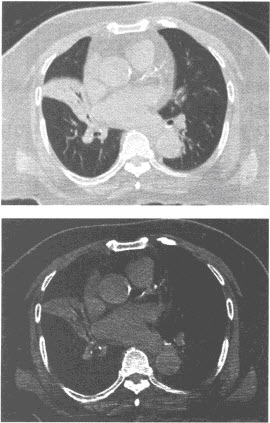

患者,男,56岁,无明显诱因突然咯血入院,作CT检查如图,病变的肺叶(段)定位应为()

A:右肺下叶内基底段

B:右肺上叶尖、后段

C:右肺中叶

D:右肺上叶前段

E:右肺下叶后基底段